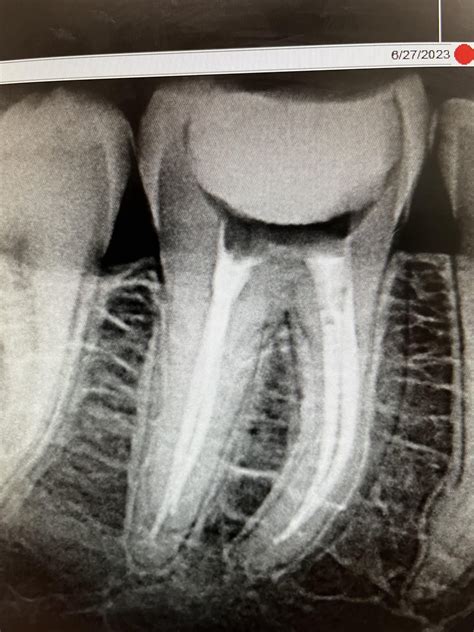

1. Diagnosis and Anesthesia: Your dentist will take X-rays to assess the extent of the infection. Local anesthesia is administered to ensure you do not feel pain during the treatment.

3. Cleaning and Shaping: The infected pulp is carefully removed using specialized dental instruments. The canals are then cleaned, disinfected, and shaped to receive a filling material.

4. Filling and Sealing: The hollowed-out canals are filled with a biocompatible material called gutta-percha, which is cemented into place.